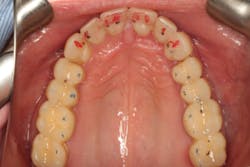

Our goal should always be to perform the least amount of dentistry needed to achieve the best possible functional results and satisfy the patient’s goals. Darren wasn’t interested in traditional orthodontics, so we elected to start with clear aligner therapy to increase the freedom in his envelope of function and improve the anterior occlusal relationship.

Orthodontics also allowed us to be more conservative in our tooth preparation. We wanted to minimize the amount of tooth structure that we had to reduce on the lingual of the maxillary incisors, since we were already missing a good amount of tooth structure from wear. Orthodontics also allowed the possibility to avoid any preparation or indirect restorations on the mandibular anterior teeth that otherwise would have been required to work out the anterior guidance. Darren was aware that we would need to make that final determination once the orthodontics treatment was completed.

Following the orthodontics, we prepared the maxillary arch for indirect restorations and placed Darren in temporary restorations. We also restored the mandibular incisal edges with direct composites to seal any exposed dentin and refine the incisal plane using a thermoplastic stent fabricated from our diagnostic wax-up. Utilizing a stent to place the direct composites on the incisal edges saved time, and we were able to obtain greater precision in the incisal edge position. Darren was then sent to the periodontist to have the gingival architecture corrected.